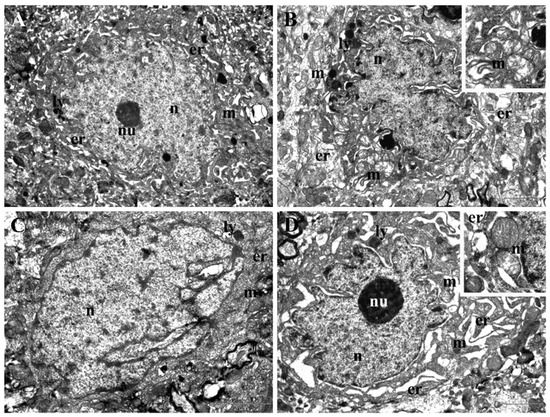

3.5. Tranmission Electron Microscopy